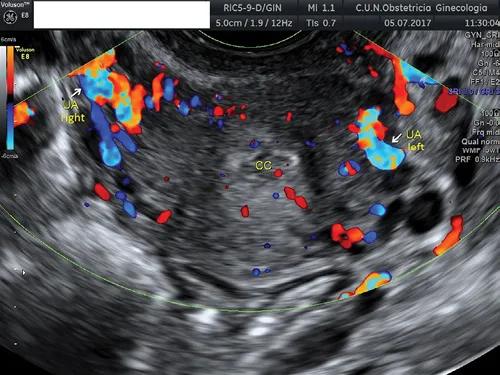

Finally, the uterine vessels can be identified laterally to the cervix, either in the longitudinal or axial planes (Figure 1.3).

Figure 1.3 Transvaginal ultrasound showing both uterine arteries (UAs) at both sides of the cervix. The cervical canal (CC) can be observed.